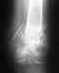

Рентгенограмма когда сделана?

Покажите сегодняшние снимки.

Снимок сделан 17.03 сразу после снятия гипса. Более свежих снимков у меня нет, но постараюсь сделать.

P.S. А что могло измениться за 10 дней?

Если эти снимки свежие, то есть смысл переделать остеосинтез - убрать пластину по возможности малоинвазивно, и сделать внутрикостный блокированный остеосинтез. Который и следовало бы сделать изначально.

Насчет полной нагрузки - как-то по этим рентгенограммам это чересчур оптимистично.

Причём сказано это было абсолютно уверенно после первого же взгляда на снимки (правда, сначала было высказано несколько отборных крепких слов в адрес оперировавшего...). Может тут повлияло плохое качество репродукции и не всё видно на прикрепленном снимке?

Александр Николаевич, доброго времени суток!

Вот что в итоге получилось, снимки от 13 января 2010 года. В феврале убрали пластину, т.к. были боли в ноге в определенных ситуациях, например, при беге. Хотелось бы, если Вам не сложно, услышать оценку оставшейся деформации,насколько это критично в будущем (сейчас вроде всё ОК). Наверное, пора бы уже и позабыть, но всё ж терзают смутные сомнения, правильно я поступил, что не стал переделывать...Спасибо заранее.

Кликните для загрузки файла 1.jpg